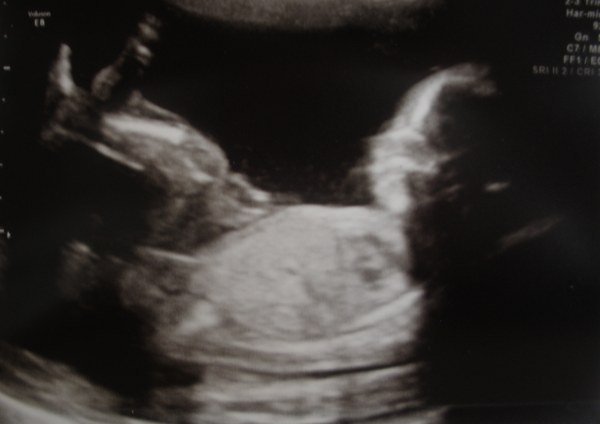

De to første er fra MD, hvor jeg var 20+